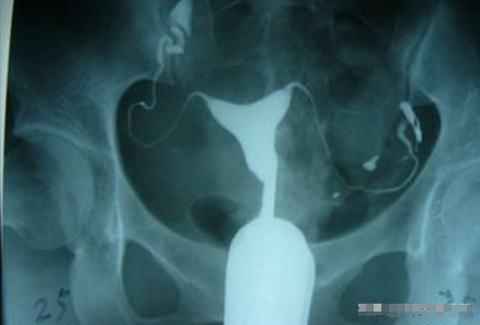

关于输卵管检查的几个问题,有要做输卵管造影的可以了解下

关于输卵管检查的几个问题:1、检查的时间:不管哪种检查,一般都安排在月经干净3-7天, 手术前3-5天禁同房。2、输卵管检查应该选择哪种方法?一般建议选择 X线下的子宫输卵管造影。3、造影有痛苦吗,可以麻醉吗?子宫输卵管造影是不孕不育诊断中常用的检查方法。检查中可能会有一定的不适,一般都能忍受。检查时最好有人陪同。目前大部分医院都没有麻醉下造影的项目。4、造影前需要做哪些检查?一般都需要先做妇科双